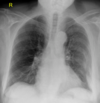

¿Qué es esto?

Neumotórax